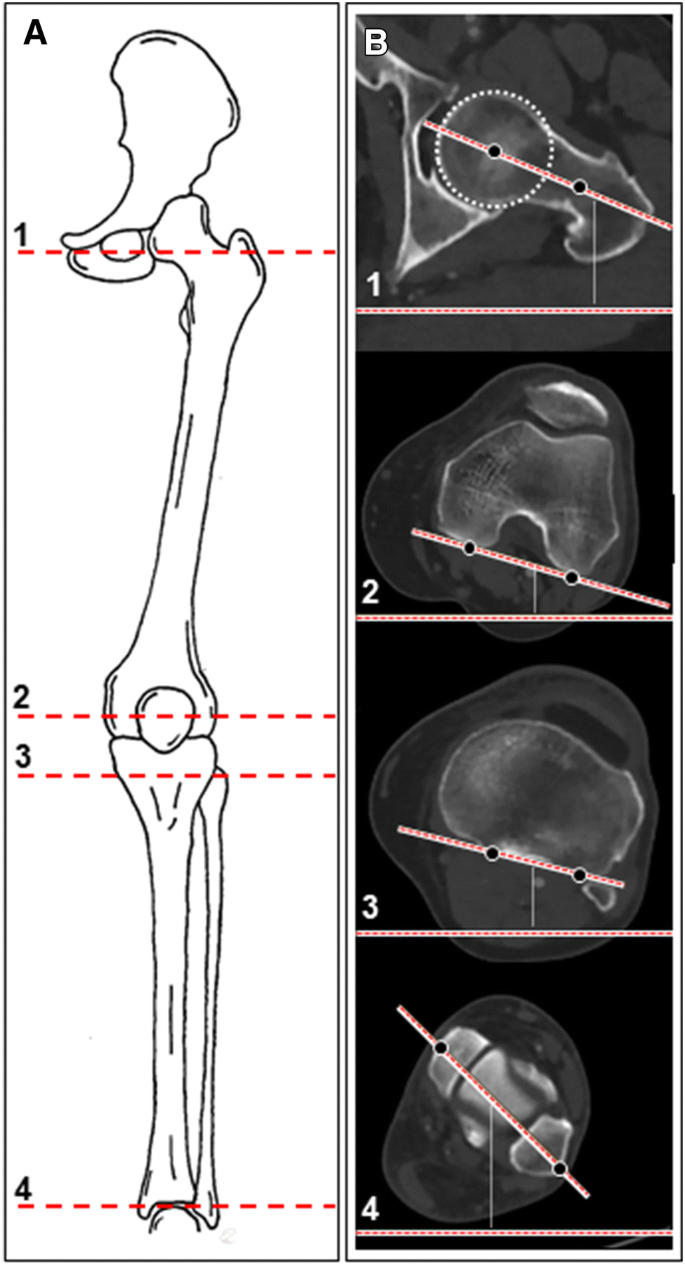

Four axes were measured, two in the femur and two in the lower leg (Fig. 2a, b): (1) femoral neck axis, (2) posterior condylar line (PCL) of the distal femur, (3) axis of the proximal tibia condyles, and (4) the bimalleolar axis.

a Exemplary sketch of left lower limb coronal view. b Lower limb axial rotation alignment measurements. (1) Femoral neck axis. (2) Distal femoral condylar axis. (3) Proximal tibial axis. (4) Distal tibial axis (bimalleolar axis)

Femoral version of the distal femur was measured by the angle formed between the line that intersects the femoral neck and the line indicating the posterior condylar line (PCL) of the distal femur. Femoral neck axis was defined according to Hernandez et al. [7] by the line between the center of the femoral head and the isthmus of the neck in a CT cut where the femoral head, isthmus of the femoral neck, and the superior border of the greater trochanter are evident. Positive values represent femoral anteversion and negative values represent retroversion of the femoral neck in relation to the PCL. Femoral anteversion equals femoral internal rotation of the PCL in relation to the femoral neck.

Tibial torsion was measured by the angle between a line connecting the posterior aspects of the proximal tibial condyles and the bimalleolar axis. The line connecting the posterior aspects of the proximal tibial condyles was set at the level of the apex of the fibula. The bimalleolar axis is drawn in a cut just below the tibial pilon’s articular surface with the medial and lateral malleoli and talar dome evident between the centers of the dense surfaces of the malleoli [6, 14]. External rotation of the tibia is represented by negative values. Positive values indicated internal rotation of distal tibia in relation to the baseline of the proximal posterior tibia plateau.